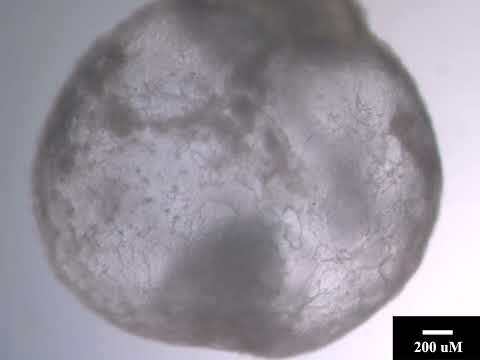

Deneyler, İsrail'deki Weizmann Enstitüsü'nde, atan bir kalbe, bağırsak ve erken bir beyin oluşumuna sahip bir embriyo oluşturabilen farelerden alınan kök hücreler kullanılarak gerçekleşti.

Dikkat çekici bir şekilde, embriyonik kök hücrelerin tam sentetik embriyolar oluşturduğunu gösteriyoruz, yani buna embriyoyu çevreleyen plasenta ve yumurta da dahil."

Hanna'nın ekibi, fare embriyolarının birkaç gün boyunca rahim dışında büyümesine izin veren mekanik bir rahim inşa etmeyi başardıktan sonra, bu nitelikteki çalışmalara daha çok öncelik vermeye başladılar.

Haberimize konu olan bu sentetik embriyo çalışma makalesi Cell 'de yayınlandı.